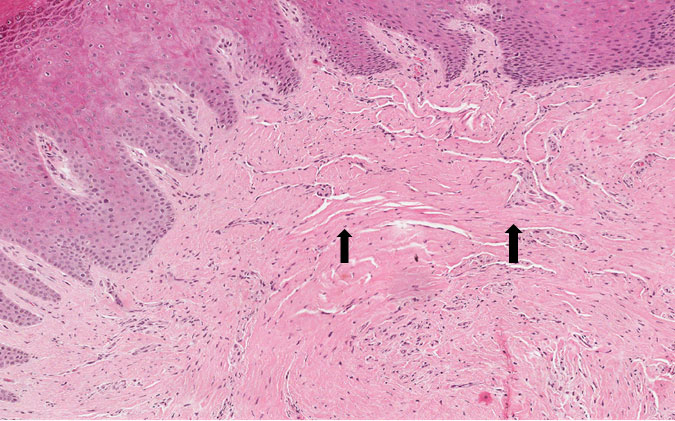

Fragmento de mucosa bucal revestida por tecido epitelial estratificado pavimentoso hiperceratinizado e hiperplasiado. Na lâmina própria, constituída por tecido conjuntivo denso observa-se exuberante deposição de fibras colágenas dispostas aleatoriamente. Focos de infiltrado inflamatório linfoplasmocitário completam o quadro.

Dados importantes para o diagnóstico

Observar o tecido epitelial hiperplasiado com cristas epiteliais alongadas (Figura 1). Infiltrado inflamatório e as áreas de fibroplasia (fibras colágenas espessas e dispersas no tecido conjuntivo — Figura 2).